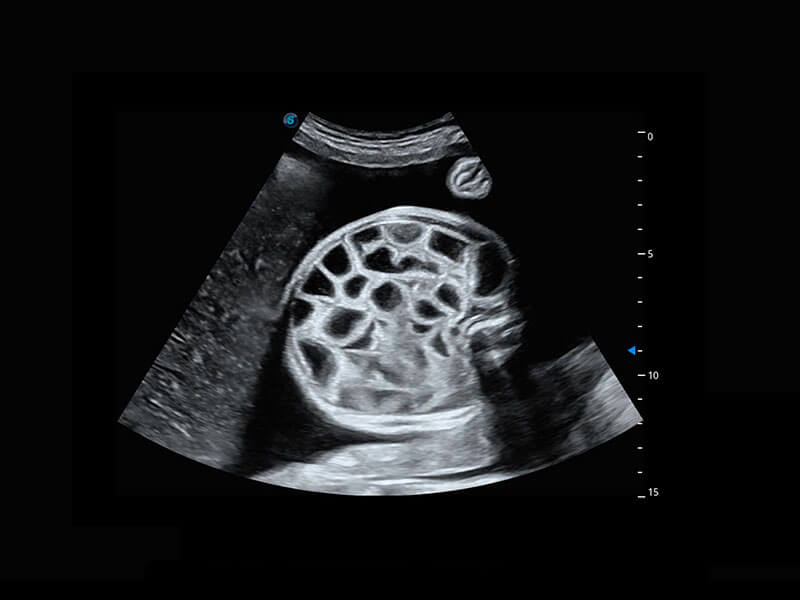

• 四腔切面

• 四腔心血流

• 右室双出口

• 胎心容积成像